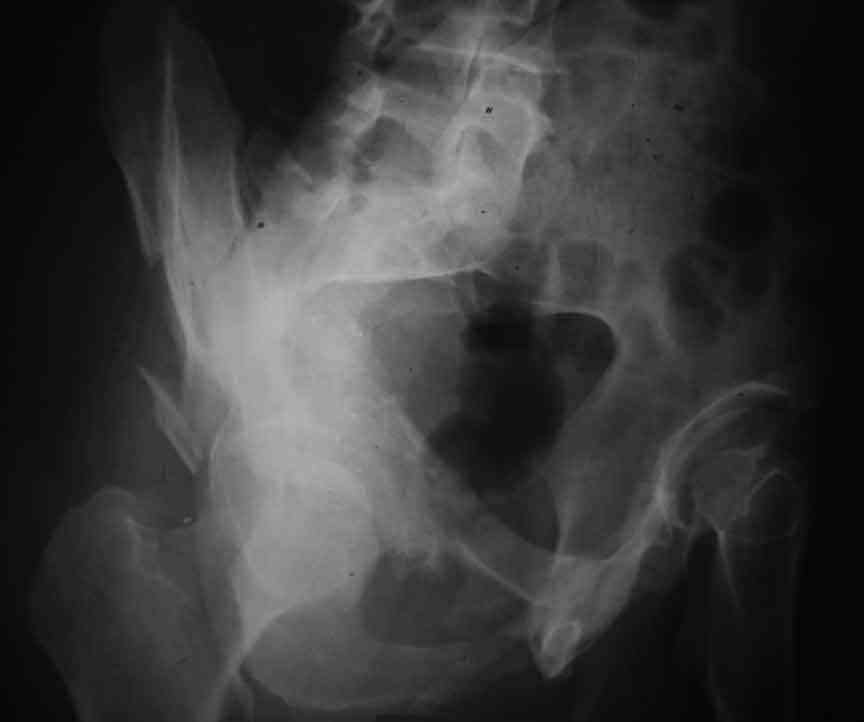

Dear Sir it looks quite difficult classify this fracture because the iliac view is not so clear.

In my opinion it is a column fracture because the obturator foramen is interrupted. There is a fracture of the posterior wall. If we assume the ap view as an iliac view it could be an anterior comun fracture plus posterior wall. It is difficult also to judge the head of the femur.

From the x rays it appears like a bicolumnar fracture with iliac extension (AO C1).

I am sending another iliac view, and a marked version of the AP I already sent. In this AP, the

proximal part of the greater sciatic notch as well as the distal parts of the ilioischial and iliopubic lines are marked with a grey interrupted line. A white interrupted line marks what could be an exit through the obturator foramen, or so I assume.